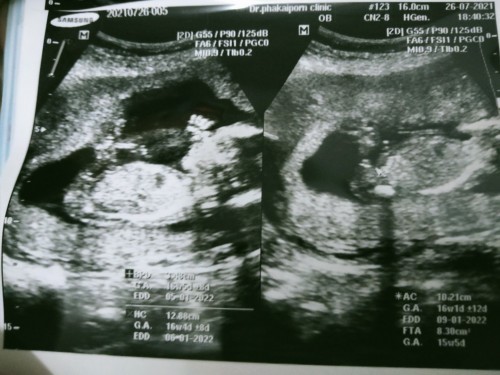

ดูที่ EDD ค่ะ จากที่ดู 9/1/65 นะคะ บางคนก็คลอดตรงกำหนด บางคนก่อน บางคนหลัง บ้านนี้เกินกำหนดมา 2 วัน ค่ะ

Eddกำหนดคลอดที่วัดจากส่วนขา Eddกำหนดคลอดที่วัดจากส่วนหัว Eddกำหนดคลอดที่วัดจากส่วนท้อง ค่ะ

EDD 👉06-01-2022 หรือ EDD👉05-01-2022

EDD ค่ะ คือ Estimated Delivery Date

วันที่6 ม.ค 65คร่